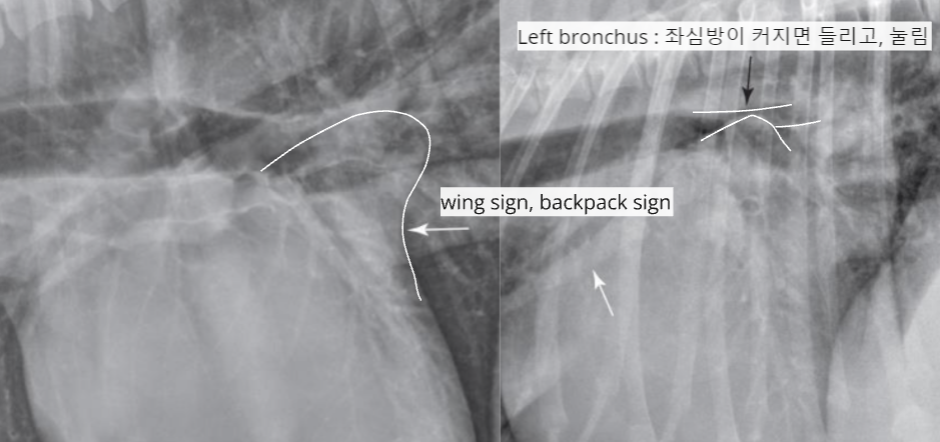

| LA enlargement |

| - wing sign, backpack sign - bow-legged cowboy sign - double wall sign HCM์์ ์ ๊ด์ฐฐ๋๋ค. |

![]() ![]() |